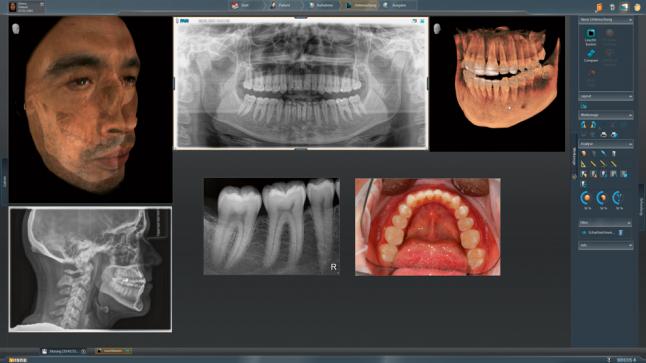

Модернизированный сенсорный экран Easypad с понятным и удобным интерфейсом позволяет выставить наилучшие параметры контрастности и разрешения. Систематизация данных по диагностике становится значительно удобнее и проще с ПО обработки изображений SIDEXIS 4, ORTHOPHOS.

1. Двух-и трёхмерные снимки совмещаются в одной программе

2. В одном окне можно сравнивать разные 3D-результаты

3. Считанные минуты уходят на просмотр анамнеза пациента.

Временная шкала Timeline – это мгновенное получение информации полного спектра проведённых обследований пациента в порядке хронологии. В результате – экономия рабочего времени и повышение качества работы в целом.

Все манипуляции, связанные с операциями имплантологического плана эффективны и безопасны. Для того чтобы наиболее оптимальным способом спланировать лечение, есть возможность совмещения цифровых слепков и рентгеновских изображений и объединения данных SIDEXIS 4 и CEREC 44.